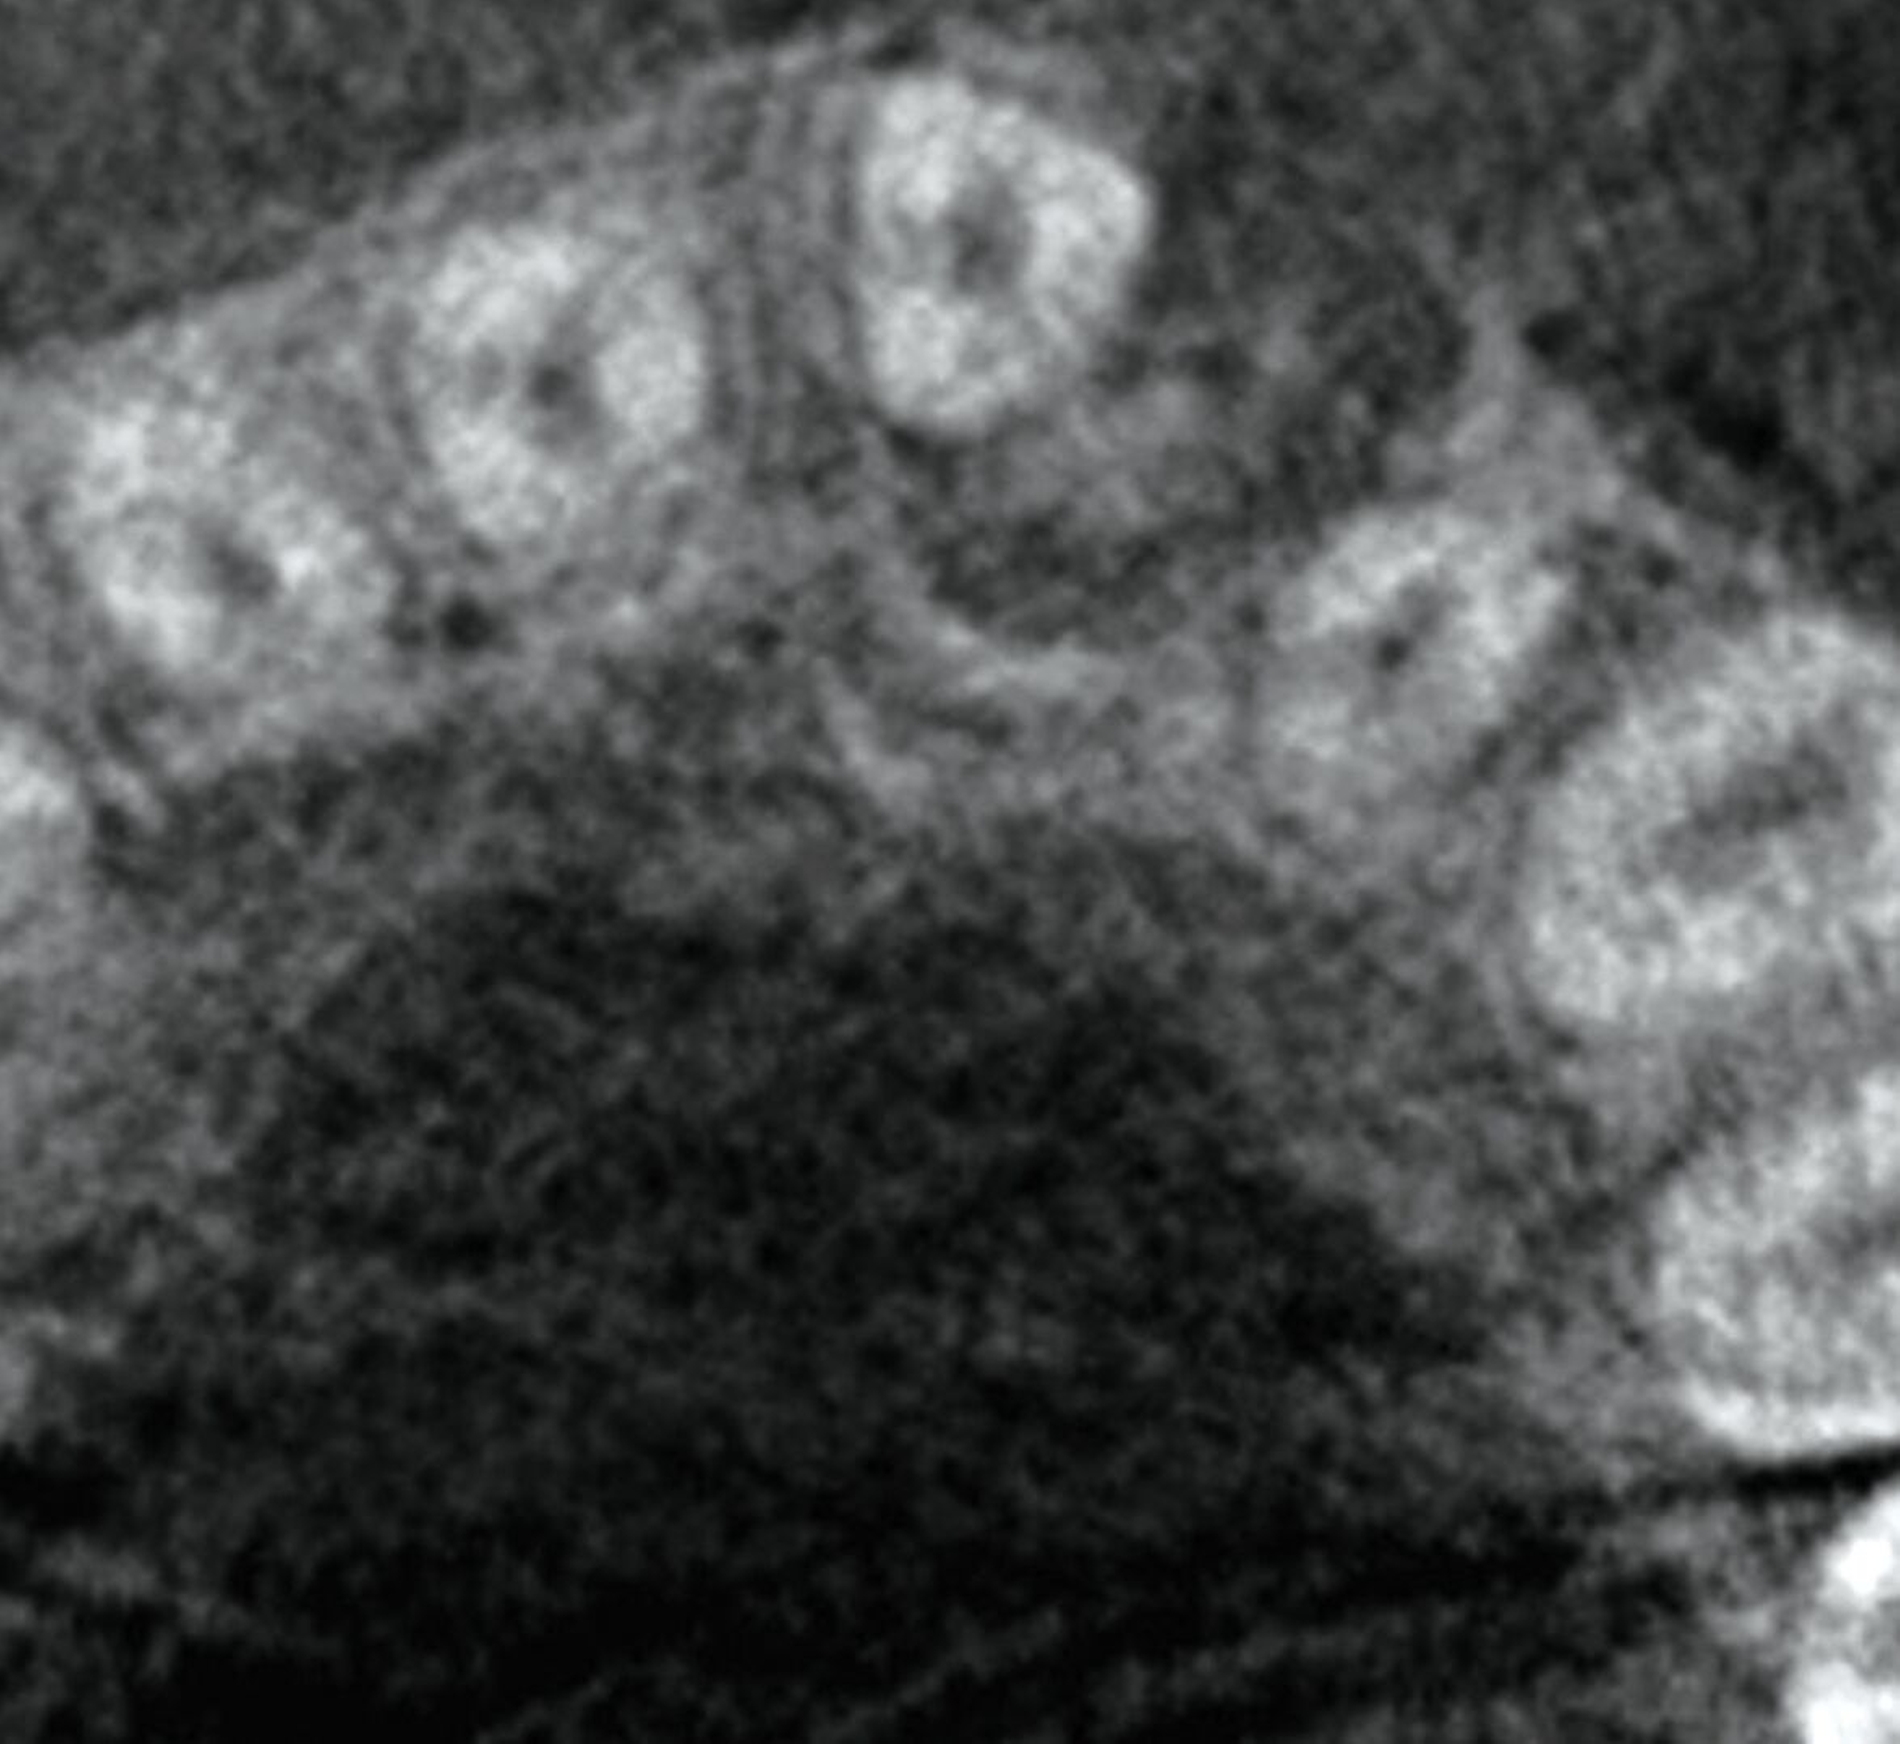

Ein zwölfjähriger Patient wurde von einem niedergelassenen Fachzahnarzt für Oralchirurgie zur operativen Entfernung einer unklaren Raumforderung im Oberkiefer überwiesen. Anamnestisch bemerkenswert war, dass Zahn 21 im Jahr 2023 durch den überweisenden Kollegen aufgrund einer begonnenen kieferorthopädischen Behandlung freigelegt wurde. Ein Jahr später zeigte sich bei der klinischen Untersuchung eine nicht-druckdolente, nicht-verschiebliche Vorwölbung der vestibulären Schleimhaut im Bereich 21-22 (Abbildung 1). In der angefertigten Digitalen Volumentomografie (DVT) ließ sich in dieser Region eine monolokuläre, relativ scharf begrenzte, radioluzente Struktur mit zentraler, diffus gefleckter Radioopazität erkennen (Abbildung 2).